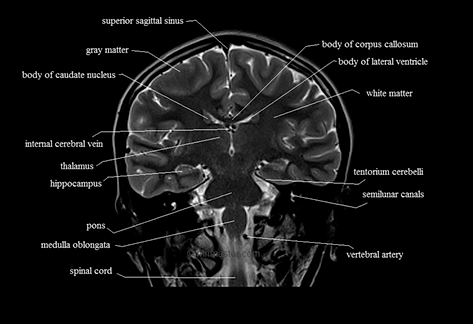

This is the coronal brain. In this slice, 13 parts of the brain are visualized.

This is the coronal brain. In this slice, 18 parts of the brain are visualized. Can you identify the missing part in this slice ?